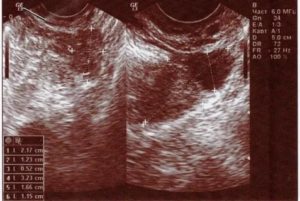

- УЗИ;

Для выявления патологии при длительной задержке месячных гинекологи выдают направление на УЗИ брюшной полости и малого таза и анализ ХГЧ. После лечения в качестве профилактики пациентки получают рекомендации по питанию и здоровому образу жизни.

- УЗИ малого таза – для определения состояния эндометрия, исключения поликистоза, прочих новообразований;